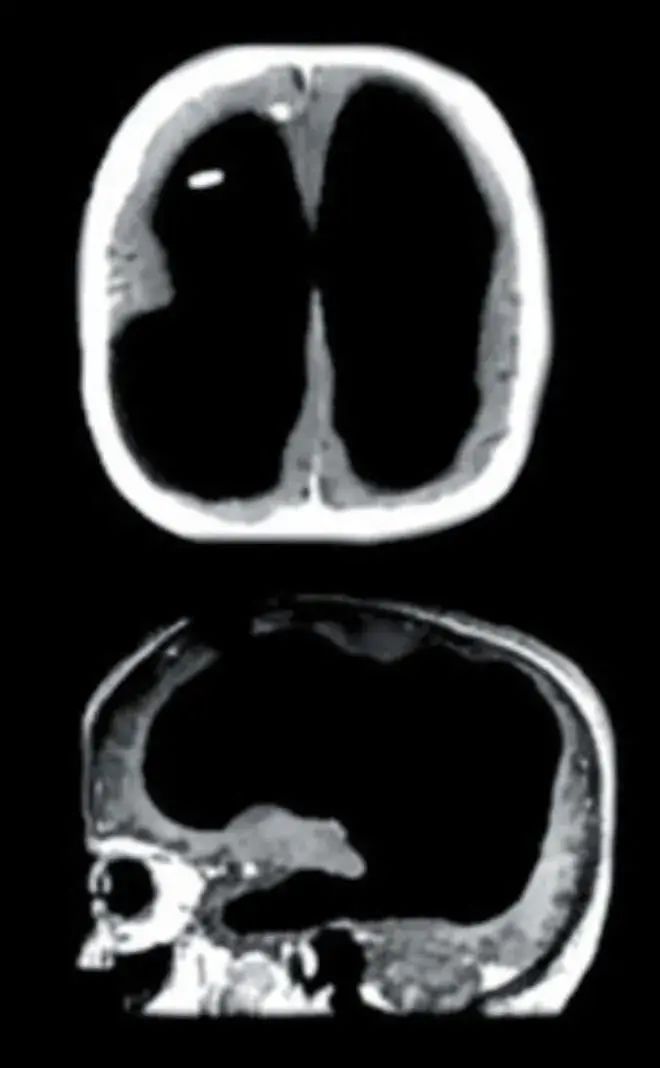

首先,意识不是大脑产生的回忆集合。不妨再做一个思维实验,假设我有两条生命轨迹,从出生开始分别生活在富人家与穷人家,因此,我将会获得两套完全不同的回忆,但“我”作为拥有并操控当前身体的意识主体是不会改变的。此外,医学界已发现多例无脑人与正常人无异的例子,说明大脑神经元产生的并非“自我"主体意识,而是回忆,认知,逻辑,想象等高级思维活动。这一切都说明意识与大脑的回忆无关。

无脑人的CT扫描图